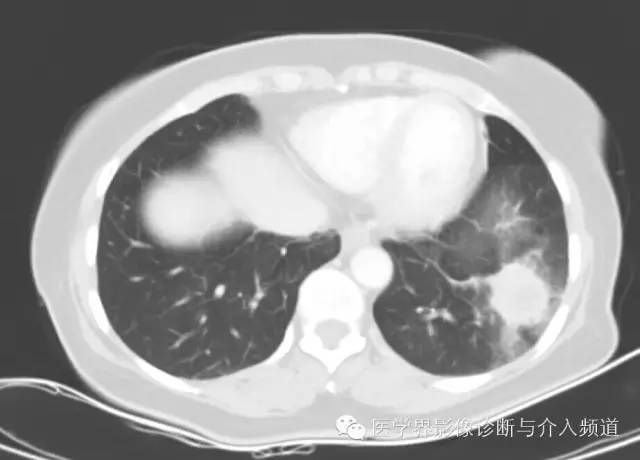

左肺下叶可见软组织密度肿块影,形态不规则,边界不光整,与胸膜粘连不清,周围肺组织呈磨玻璃密度改变,病变内部不均匀强化,低密度区不强化。

病变形态:圆形、椭圆形,单发,边缘光整,境界清晰,毛刺征、空洞、胸膜凹陷征罕见,少数可见浅分叶。

其他征象:钙化、囊变(与出血有关)、周围晕征(非特征性)、周围肺组织肺气肿、增强扫描明显均匀强化(与病变内血管瘤区、乳头区、硬化区、实变区有关)、贴边血管征(肿瘤推挤周围血管,较具特征性)、纵膈及肺门淋巴结(罕见,但有报道)。